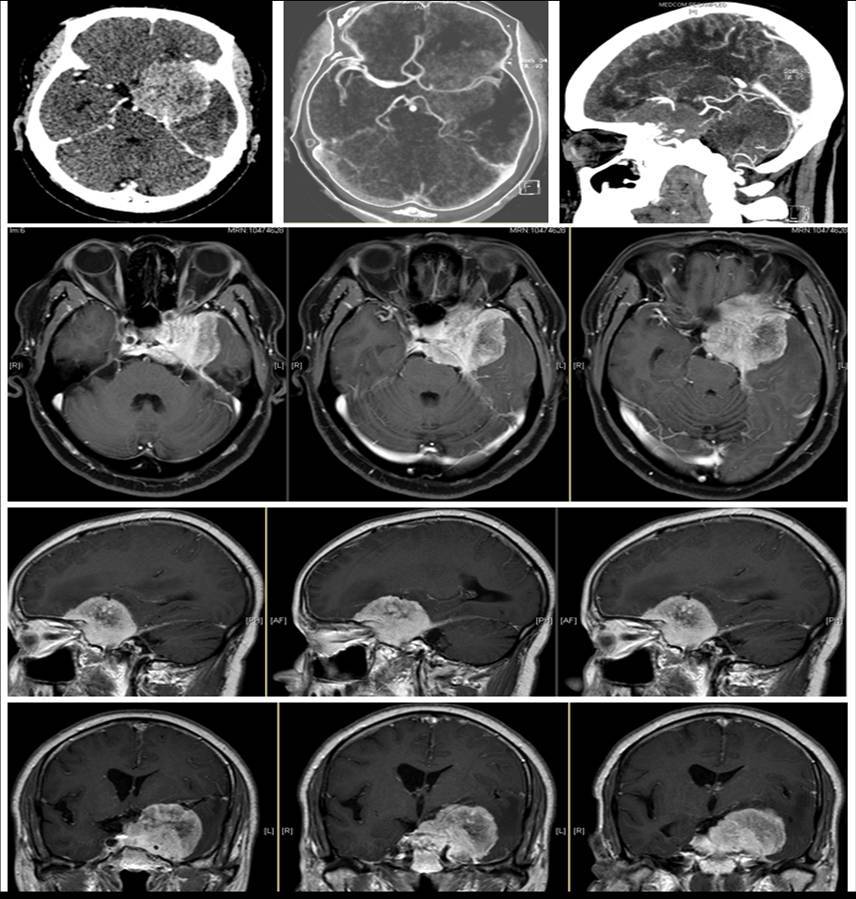

神经外科团队成功实施一例大型颅底肿瘤切除术